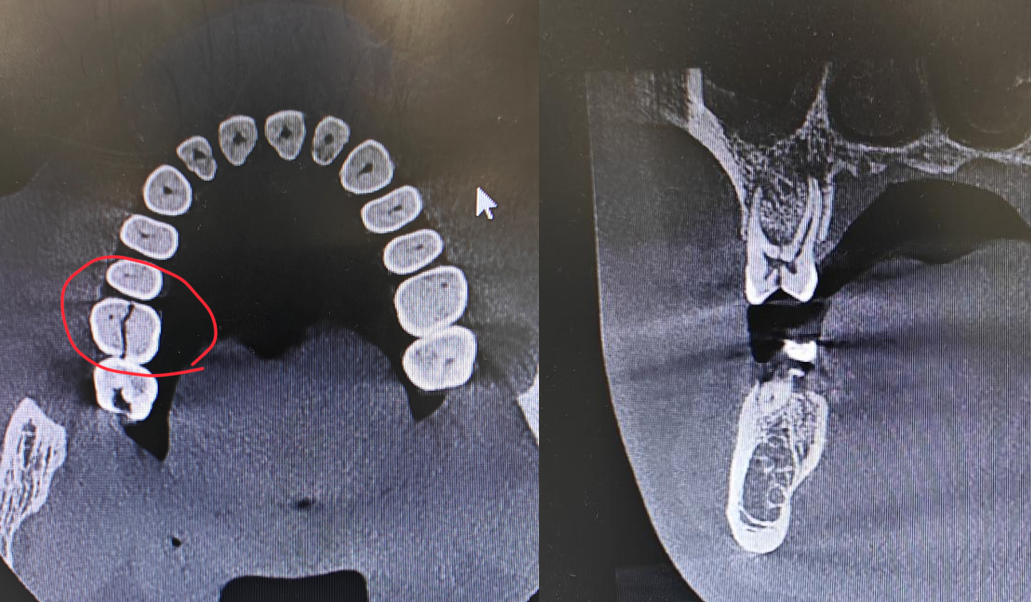

近日,一患者到西安市红会医院口腔科就诊,检查发现其牙齿咬合面存在裂纹,拍片后进一步确诊牙齿已裂为两半,无法保留。接诊医生告知患者,这颗牙齿已无保留价值,需先拔除再择期修复,患者对此十分不舍。拔牙后患者向医生坦言,自己深感后悔 —— 这颗牙齿其实已不适一年,直到近期症状加重、无法咬合,才不得不来就医。医生表示,若患者能尽早到口腔科就诊,这颗牙齿本可得到保留。

牙隐裂,顾名思义,是指牙齿表面出现的一些细微、不易被发现的非生理性裂纹。这些裂纹可以浅至牙釉质表层,也可以深达牙本质深层,甚至贯穿牙髓(牙神经),或者导致牙根纵裂。

完全劈裂(裂纹延伸至牙根):非常遗憾,这种情况下牙齿通常无法保留,只能拔除。后续需要通过种植牙、固定桥或活动义齿等方式来修复缺失的牙齿。